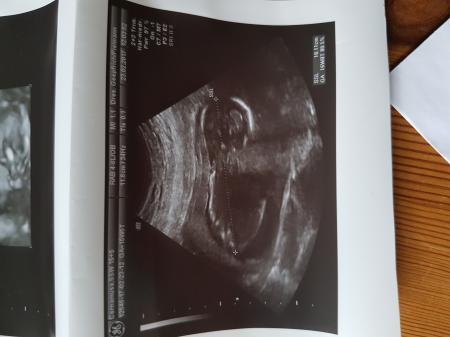

Zwergi ist jetzt knapp 13 cm lang und ca. 150g schwer. Gewunken hat es auch.... Nur zwischen die Beine durften wir nicht schauen. Schade, dass man hier keine Videos hochladen kann- habe eins bekommen Am 02.03. Habe ich den grossen zuckertest Am 09.03. Termin und am 28.03. Termin zum organscreening. Hier die Bildchen von Zwergi LG

Bild zu Zurück vom Fa..... - Forum für August - Mamis